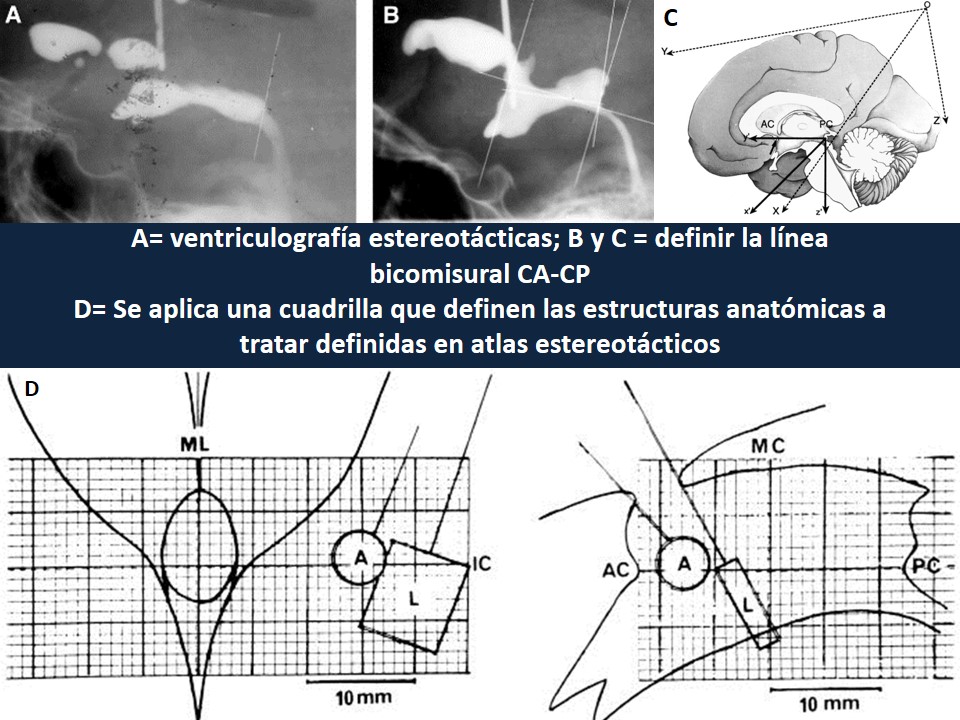

Metodología Estereotáctica o Estereotaxia

Dr. Guillermo Larrarte